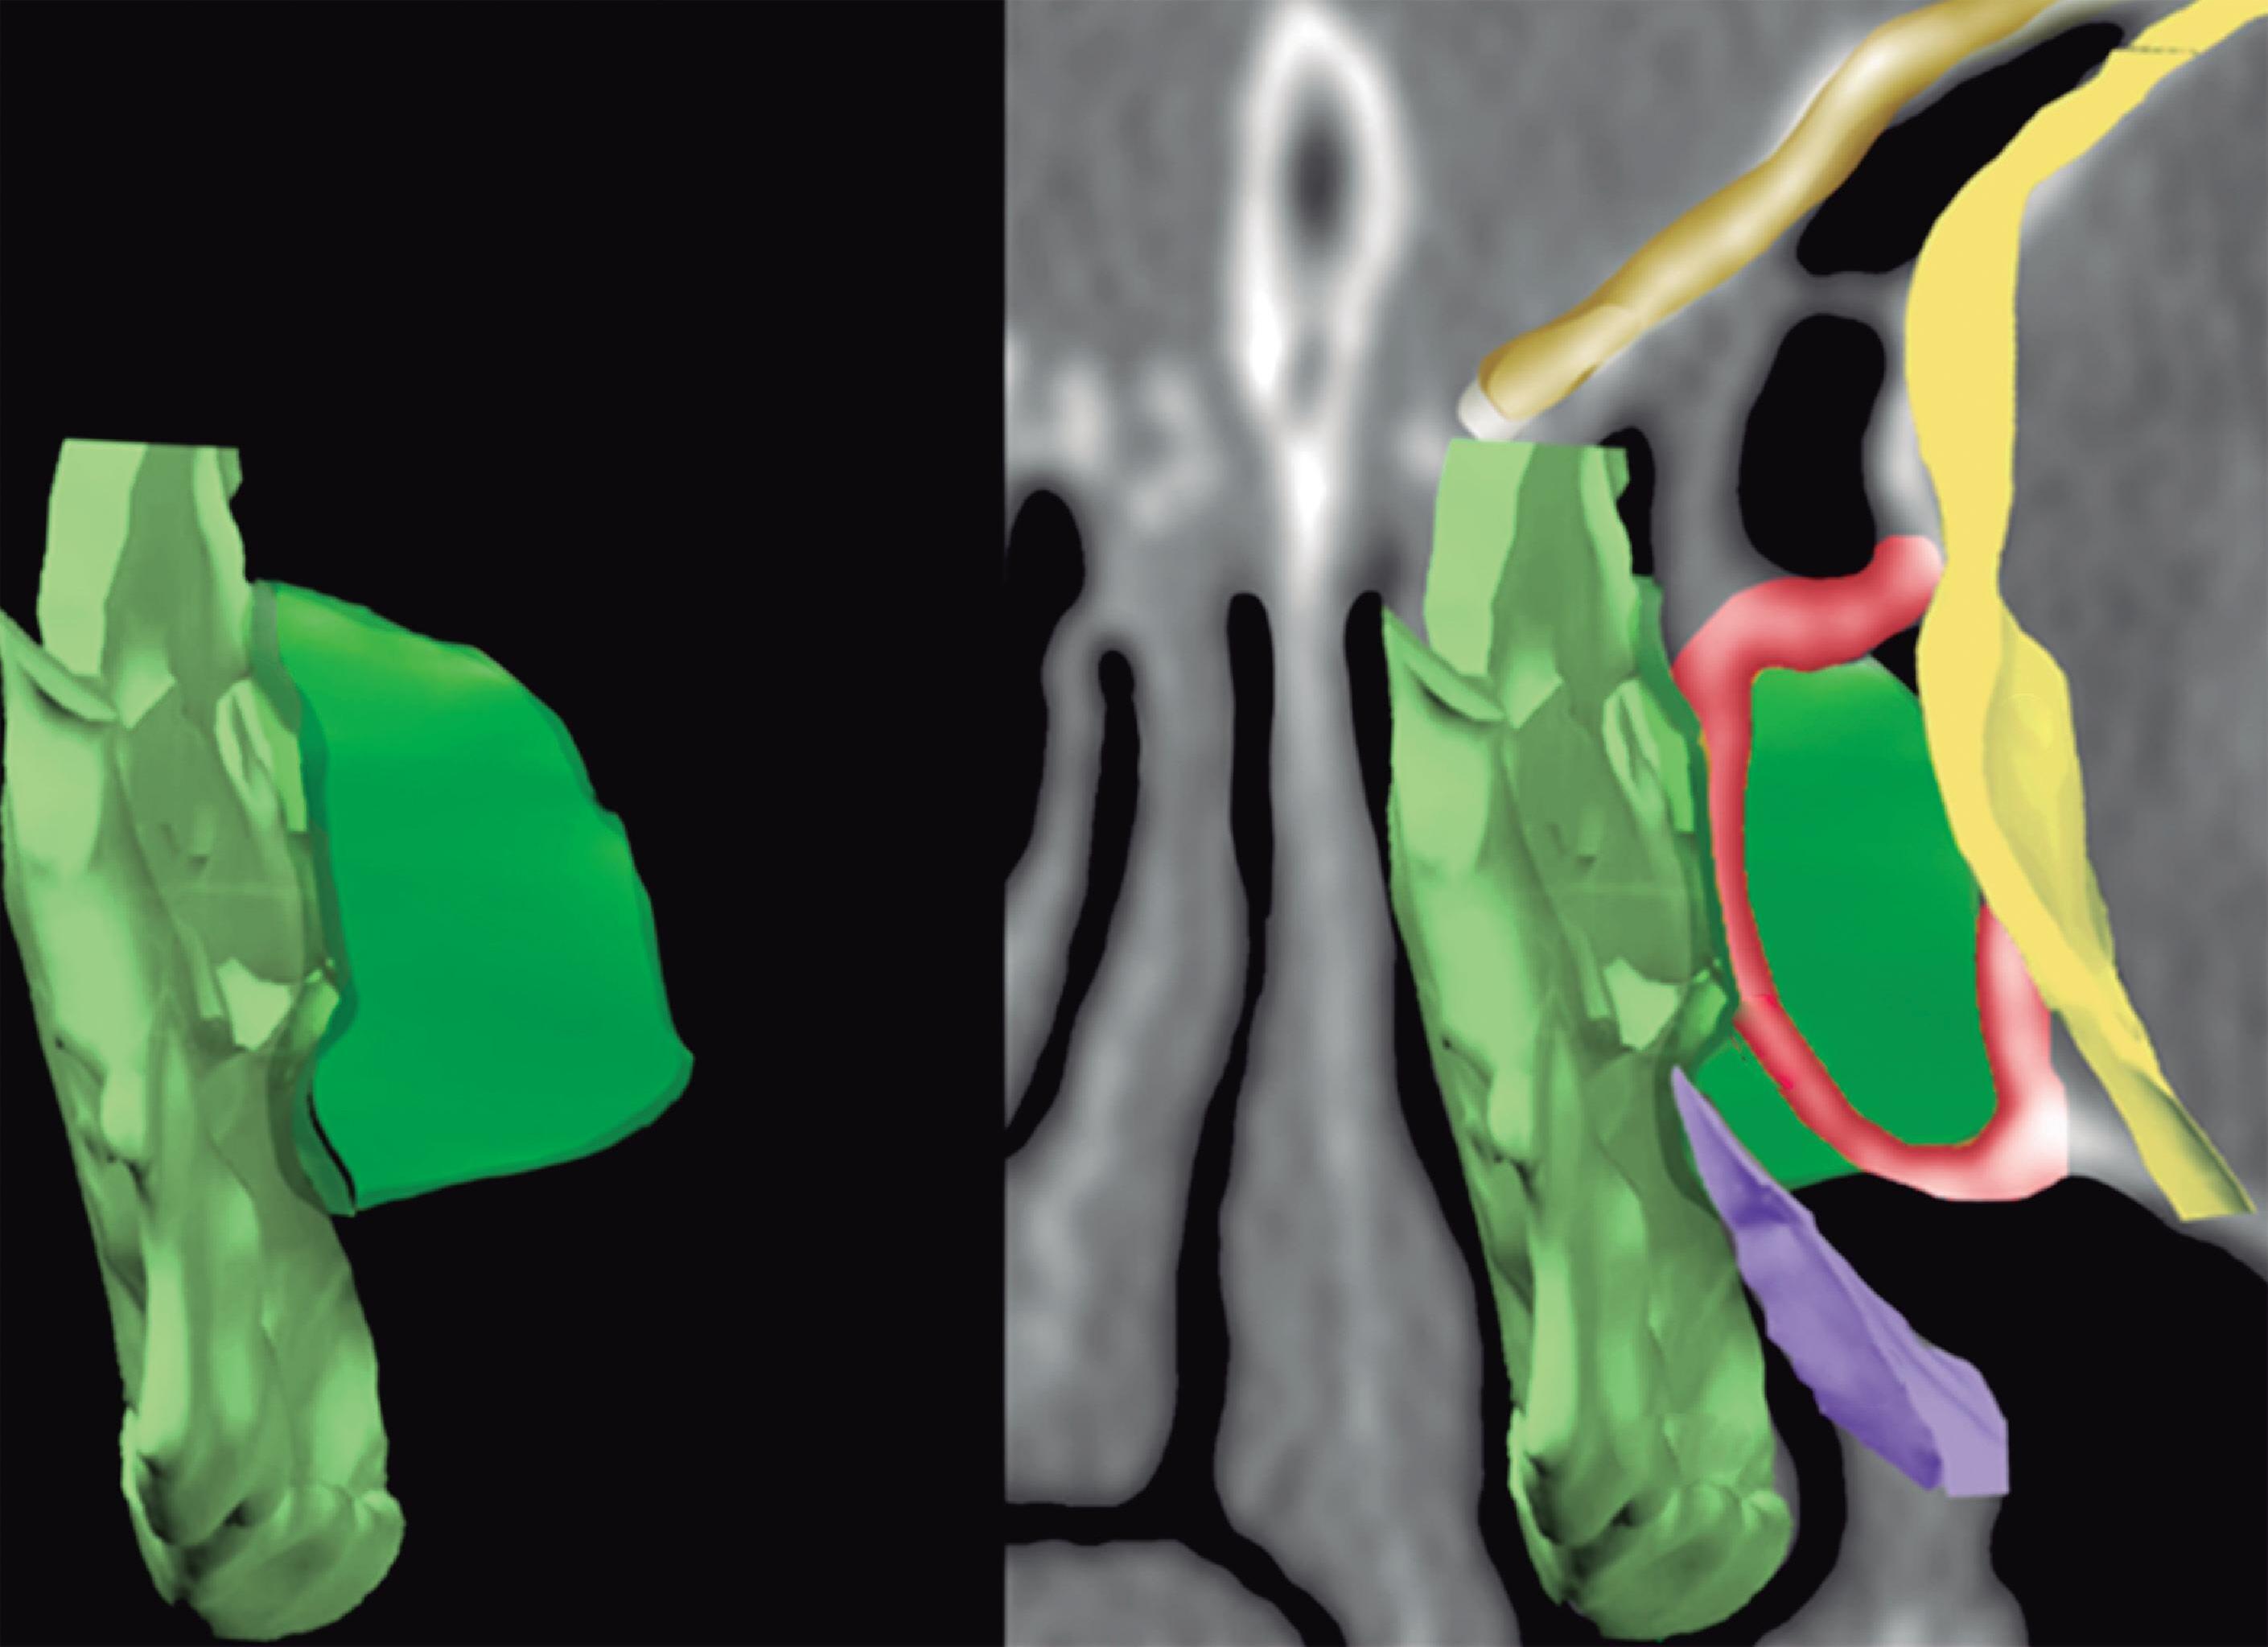

Fig. 1-20. Reconstrução tridimensional de TC demonstrando a lamela basal situada posteriormente à bulha etmoidal, acoplada à parede medial da órbita, fechando a câmara anterior: verde – concha média; vermelho – bulha etmoidal; amarelo – parede medial da órbita; lilás – processo uncinado.

A lamela basal da concha média é a parede anterior do meato superior que é limitado posteriormente pela lâmina basal da concha superior, que será o limite anterior do meato supremo que vai ser limitado posteriormente pela face anterior e lateral do seio esfenoidal.

Cada concha tem sua lamela conectada à parede medial da órbita, mas podem também se conectar ou seguir em direção à base do crânio.